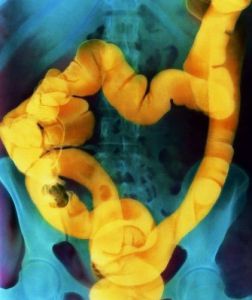

Ирригоскопия — рентгенологическое исследование толстой кишки при ретроградном заполнении ее рентгеноконтрастной взвесью.

Под рентгенологическим контролем постепенно заполняют рентгеноконтрастной взвесью толстую кишку и производят обзорные и прицельные снимки всех ее отделов в разных положениях больного. На следующем этапе, после удаления из толстой кишки рентгеноконтрастной взвеси, исследуют рельеф слизистой оболочки кишки.

На заключительном этапе ирригоскопии, особенно при подозрении на опухоль толстой кишки, исследование проводят при дозированном заполнении кишки воздухом, используя аппарат Боброва (двойное контрастирование).